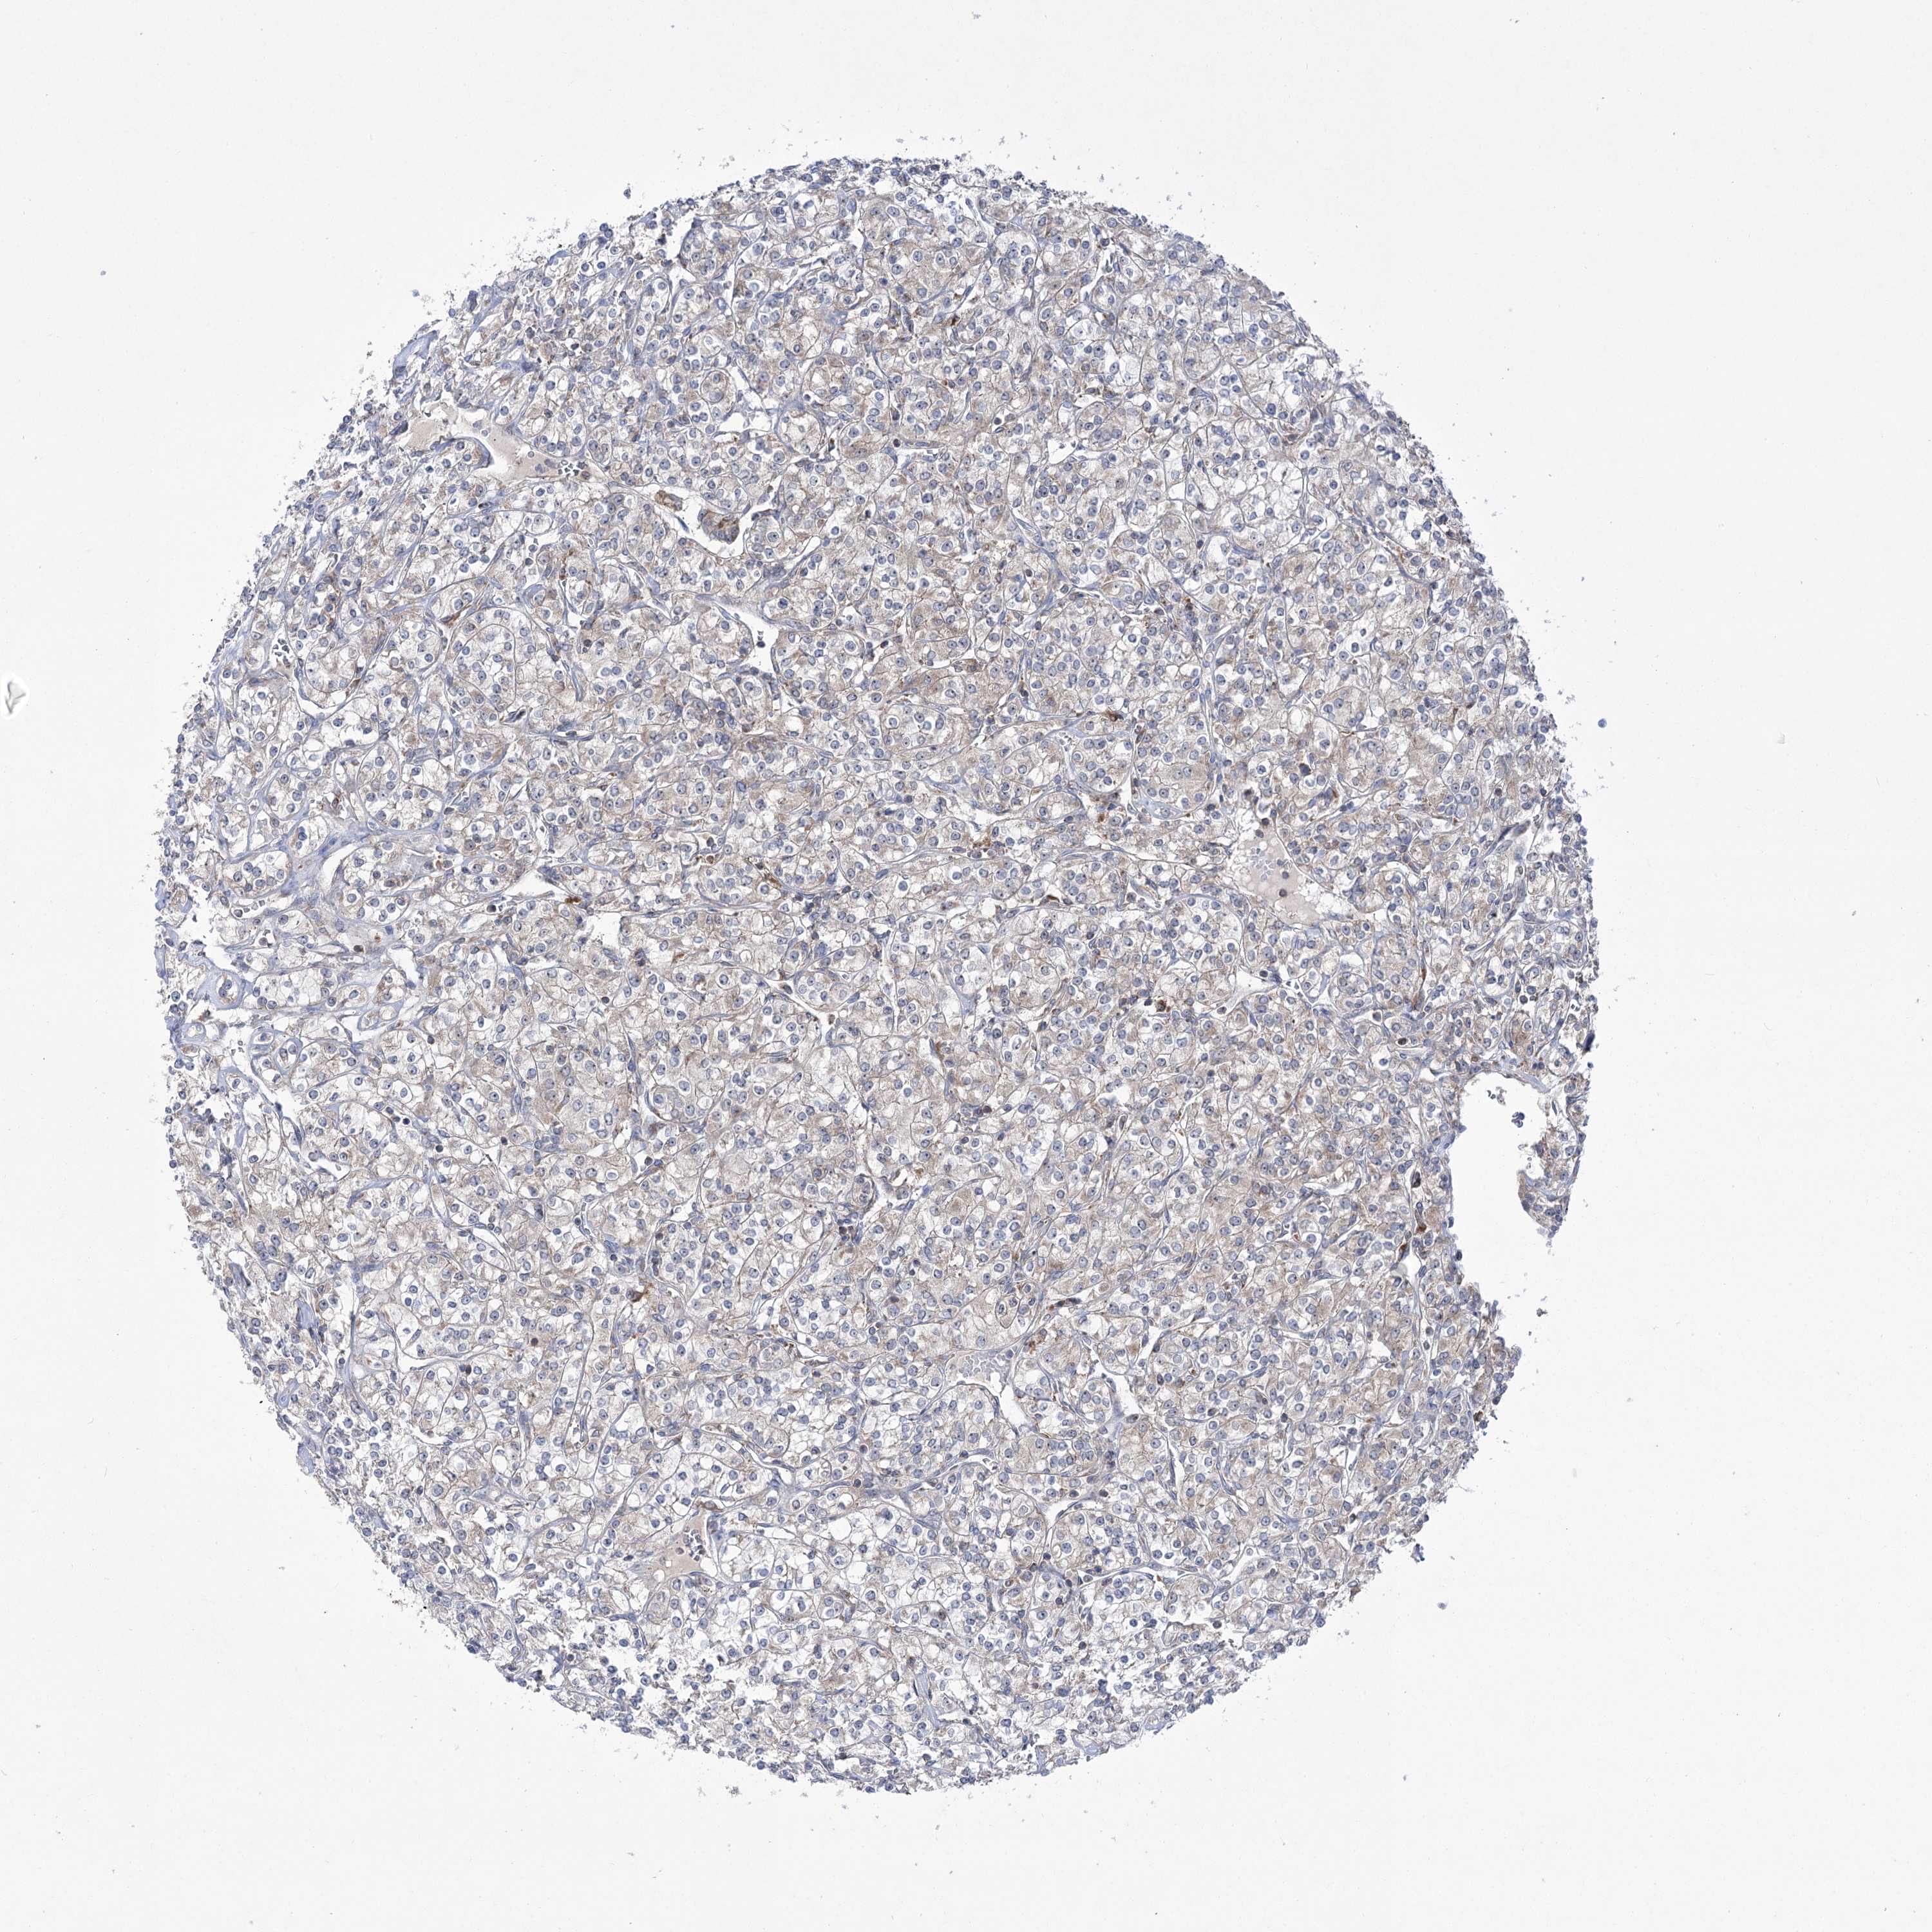

KIDNEY RENAL CLEAR CELL CARCINOMA (VALIDATION) - Interactive survival scatter ploti

The Survival Scatter plot shows the clinical status (i.e. dead or alive) for all individuals in the patient cohort, based on the same data that underlies the corresponding Kaplan-Meier plots. Patients that are alive at last time for follow-up are shown in blue and patients who have died during the study are shown in red.

The x-axis shows the expression levels (FPKM) of the investigated gene in the tumor tissue at the time of diagnosis. The y-axis shows the follow-up time after diagnosis (years). Both axes are complimented with kernel density curves demonstrating the data density over the axes. The top density plot shows the expression levels (FPKM) distribution among dead (red) and alive patients (blue). The right density plot shows the data density of the survived years of dead patients with high and low expression levels respectively, stratified using the cutoff indicated by the vertical dashed line through the Survival Scatter plot. This cutoff is automatically defined based on the FPKM cutoff that minimizes the p-score. The cutoff can be changed by dragging the vertical line or by entering a cutoff value in the square labeled "Current cut-off".

Under the Survival Scatter plot the p-score landscape (black curve; left axis) is shown together with dead median separation (red curve; right axis). Dead median separation is the difference in median mRNA expression between patients who have died with high and low expression, respectively. It is calculated as follows: median FPKM expression of dead patients with high expression - median FPKM expression of dead patients with low expression. This is intended to aid the user in visually exploring custom cutoffs and the associated p-scores and dead median separation.

Individual patient data is displayed and can be filtered by clicking on one or more of the category buttons on the top of the page. Categories describing expression level and patient information include: high, low, alive, dead, female, male and tumor stages. The scale of the x-axis can be toggled between linear and log-scale by clicking on the "x log" button. Mouse-over function shows TCGA ID, patient information and mRNA expression (FPKM) for each patient.

& Survival analysisi

Kaplan-Meier plots summarize results from analysis of correlation between mRNA expression level and patient survival. Patients were divided based on level of expression into one of the two groups "low" (under cut off) or "high" (over cut off). X-axis shows time for survival (years) and y-axis shows the probability of survival, where 1.0 corresponds to 100 percent.

ZNF622 is not prognostic in Kidney Renal Clear Cell Carcinoma (validation)

Best expression cut offi

Based on the FPKM value of each gene, patients were classified into two groups and association between prognosis (survival) and gene expression (FPKM) was examined. The best expression cut-off refers the FPKM value that yields maximal difference with regard to survival between the two groups at the lowest log-rank P-value. Best expression cut-off was selected based on survival analysis .

When clicking on this number, the vertical dashed line indicating cut-off, the interactive survival plot, and the Kaplan-Meier curve will be adjusted to show results based on the best expression cut-off.

: 28.31

TCGA RNA samplesi

RNA-seq data is reported as average FPKM (number Fragments Per Kilobase of exon per Million reads), generated by the The Cancer Genome Atlas (TCGA) .

Normal distribution across the dataset is visualized with box plots, shown as median and 25th and 75th percentiles. Points are displayed as outliers if they are above or below 1.5 times the interquartile range. FPKM values of the individual samples are presented next to the box plot.

Average pTPM 35.0

Number of samples 100